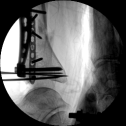

2.CO接骨機器人持續(xù)牽引維持復(fù)位,選擇前外側(cè)切口對前外側(cè)骨塊進(jìn)行撬撥復(fù)位,并用克氏針進(jìn)行臨時固定。C臂透視復(fù)位滿意,放置兩塊鋼板進(jìn)行固定。

3.在脛骨近端穿入一根克氏針,連接CO外固定架進(jìn)行固定,并外踝處穿入一根克氏針進(jìn)行固定。C臂透視位置滿意,縫合結(jié)束手術(shù)。